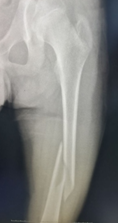

股骨干骨折弹性髓内钉固定术前

手术切口(仅为一个小孔)

股骨干骨折弹性髓内钉固定术后